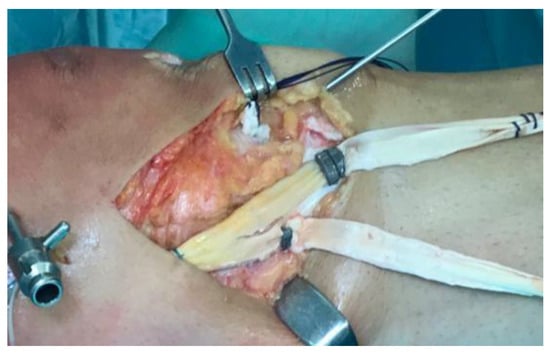

- Direct repair: reattaching the MCL using screws and washers or a suture anchor [4].

- Lind (Danish) reconstruction: a semi-anatomic “double-bundle” reconstruction of the sMCL and POL. The patient’s semitendinosus autograft is harvested, preserving the tibial insertion, and is fixed proximally at the sMCL insertion to recreate the sMCL and distally on the tibia to mimic the POL. This method does not aim for exact replication of ligament insertions but reconstructs two structures with a single autograft and uses only one femoral tunnel [8].

- Hughston reconstruction: focuses on capsular and POL “plication” to restore natural soft-tissue tension. It leverages anatomical features of the posteromedial corner, notably the proximal portion of the sMCL, which has significant soft-tissue adhesions to the medial femoral condyle that can help disperse tension. It is valued for simplicity and cost-effectiveness [54].

- New reconstruction option: the latest “triple-stranded” MCL reconstruction uses three different grafts aimed at recreating the sMCL, POL, and dMCL [55].